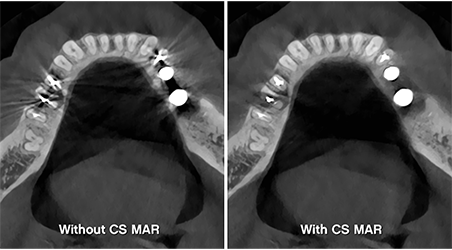

3. เทคโนโลยีลดสิ่งรบกวนจากโลหะ (CS MAR) ลดอาร์ติแฟกต์จากโลหะในภาพ CBCT พร้อมระบบเปรียบเทียบภาพก่อน-หลังเปิดใช้ CS MAR ได้แบบเรียลไทม์